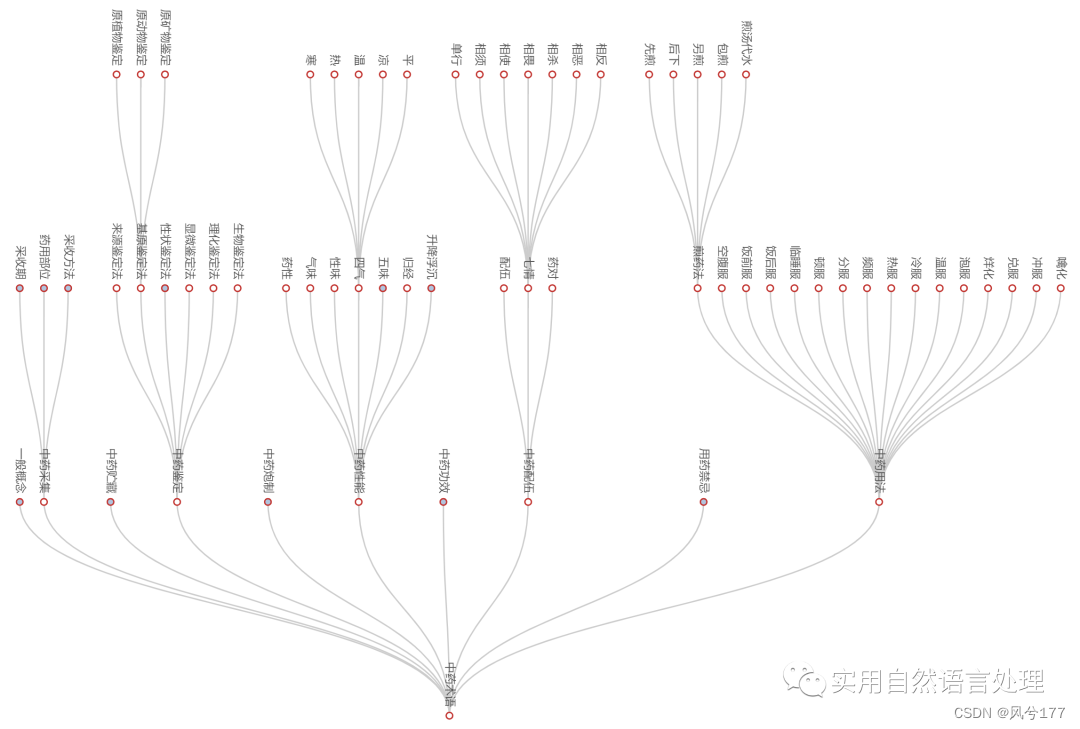

2.4 中药术语知识图谱可视化

中医术语知识为层次结构,其树形图展示如下。

自底向上的树图(部分节点展开)